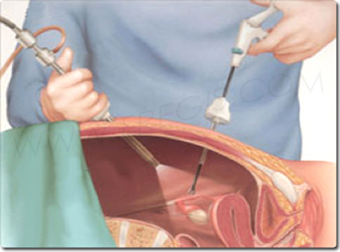

L’hystéroscopie est une intervention qui utilise un hystéroscope, un tube fin équipé d’une petite caméra, pour visualiser la cavité utérine. Cette techniques est utilisée pour établir un diagnostic précis et guider les traitements. Selon le besoin, il existe deux types :

- Hystéroscopie diagnostique : Réalisée sans anesthésie, elle permet d’observer l’utérus et de procéder à certaines biopsies.

- Hystéroscopie opératoire : Elle se fait sous anesthésie et permet de retirer des anomalies constatées, telles que des fibromes ou des polypes.

Le déroulement de l’hystéroscopie est généralement simple. Lors d’une hystéroscopie diagnostique, l’examen est effectué sans anesthésie avec un hystéroscope de petite taille. Selon les résultats obtenus, des biopsies peuvent être réalisées pour des analyses complémentaires. En revanche, l’hystéroscopie opératoire, pratiquée sous anesthésie, permet non seulement de diagnostiquer mais aussi de retirer des lésions identifiées. Les gynécologues suivent un protocole rigoureux pour assurer la sécurité et le confort des patientes pendant l’examen.